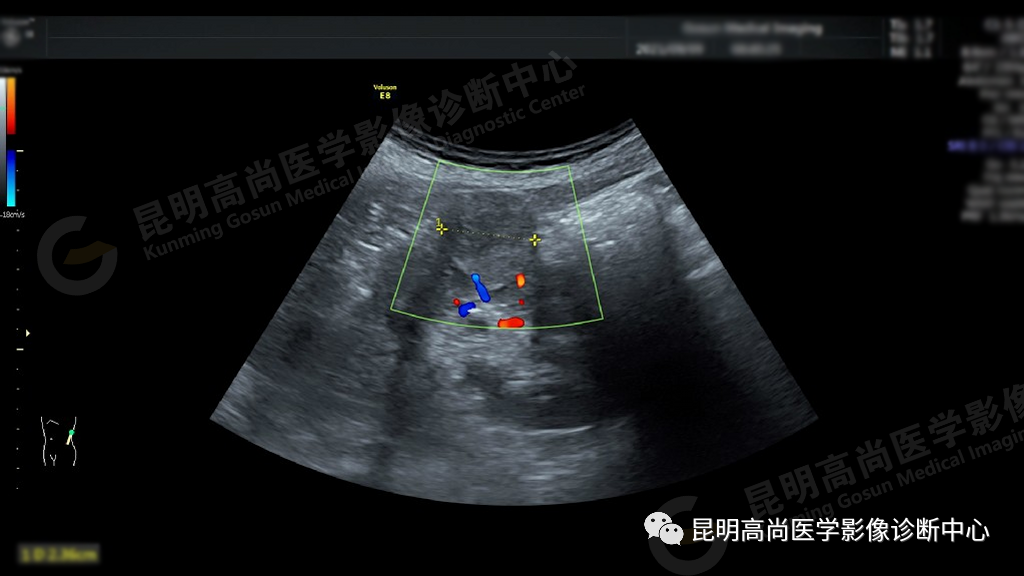

超声所见:左肾切面大小正常,形态失常,轮廓不规则局部突起,在左肾中部肾实质内可见一个大小约 25 mm×24 mm 肿块图像,形状呈圆形,内部为中等回声,分布不均质,边界清楚,似有包膜,后方回声无变化,彩色多昔勒显示:内可见丰富血流信号,肾门处未见肿大的淋巴结。

超声提示:左肾实质性占位病变,性质待查,建议进一步检查。